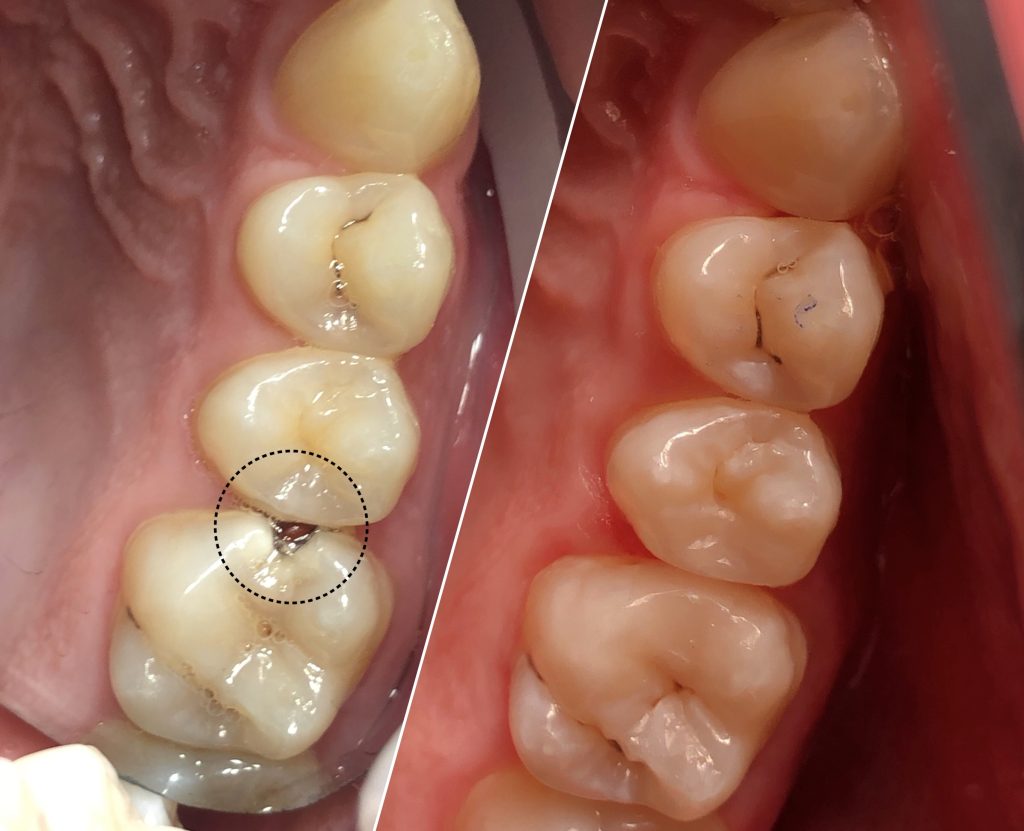

• Художественная реставрация фронтального и бокового участка зубов

2023 год – «Прямая композитная реставрация фронтальной группы зубов» Владимир Мальченко